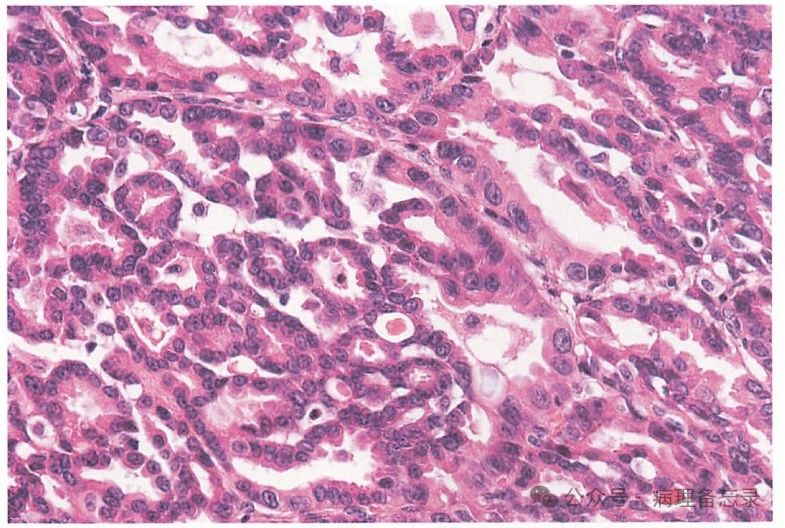

细胞异型大,核呈空泡状,核内可见核仁

细胞排列密集,异型大,核呈空泡状,核内可见核仁